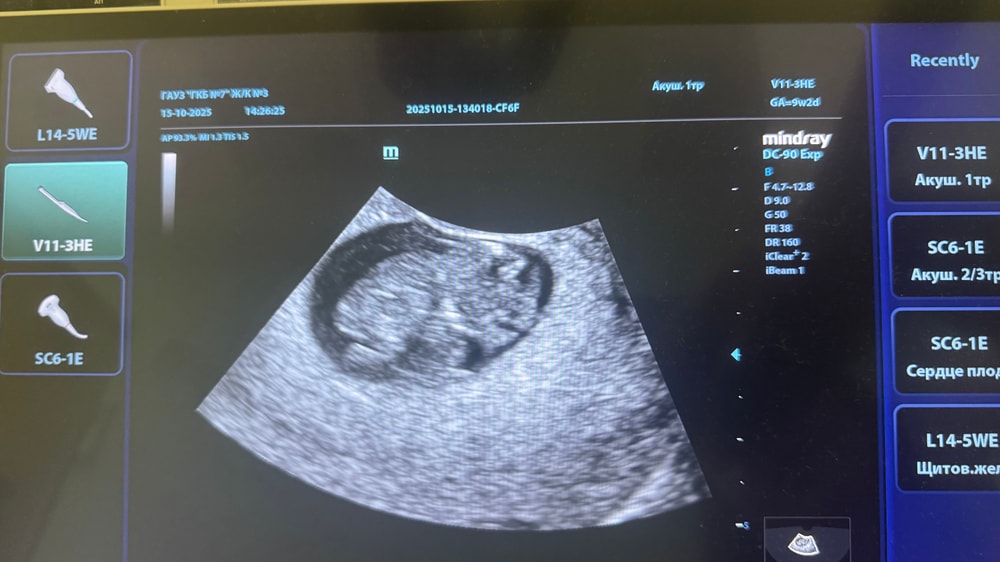

перед постановкой сделали узи 🙌🏻ктр 26мм

Какой уже человечек, загляденье 😍